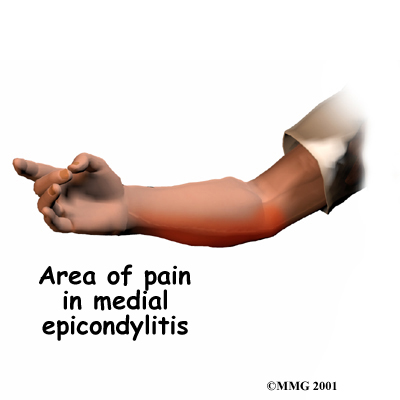

Medial Epicondylitis

Medial epicondylitis, also called:

Golfer's Elbow

affects the area where the tendons of the elbow attach to bone on the inside of the elbow. It causes pain when using the wrist and hand.